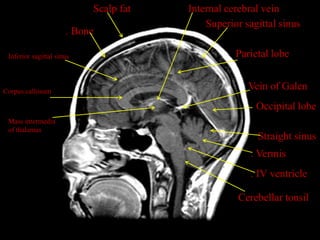

Scalp fat   Internal cerebral vein

Superior sagittal sinus

. Bone

Inferior sagittal sinus                          Parietal lobe

Corpus callosum

Vein of Galen

Occipital lobe

Mass intermedia

of thalamus

Straight sinus

. Vermis

. IV ventricle

Cerebellar tonsil

Scalp fat Internal cerebral vein Superior sagittal sinus . Bone Inferior sagittal sinus Parietal lobe Corpus callosum Vein of Galen Occipital lobe Mass intermedia of thalamus Straight sinus . Vermis . IV ventricle Cerebellar tonsil